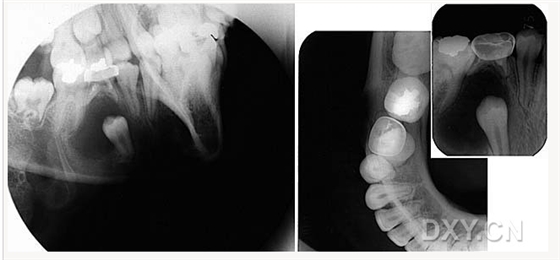

頜骨骨折

牙源性鈣化囊腫

牙瘤!

牙源性鈣化囊腫    牙瘤!

牙瘤